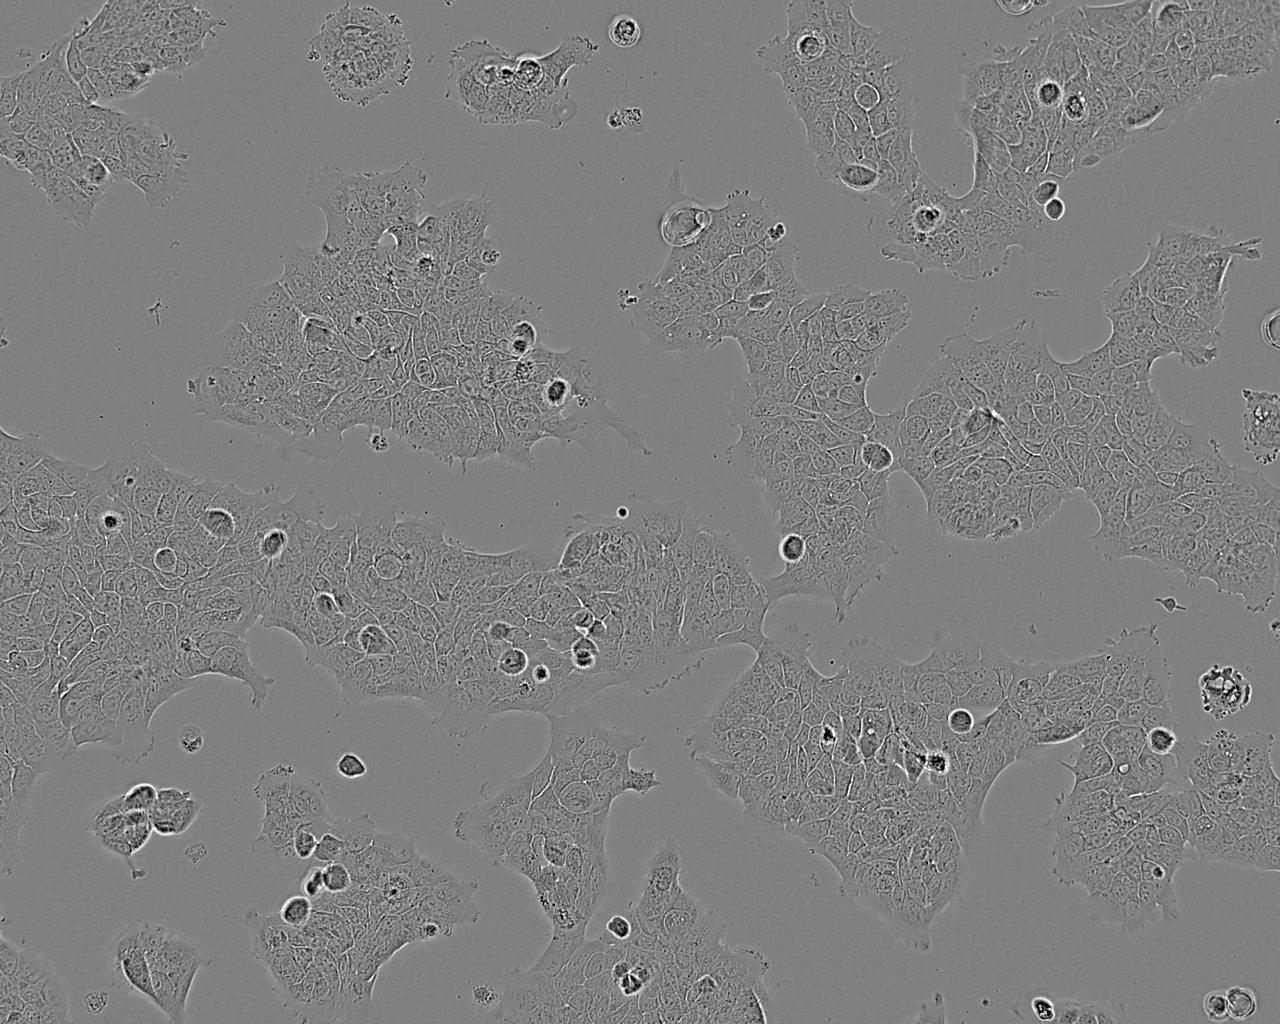

形态特征 上皮细胞样

生长特征 贴壁

培养要点 细胞成片生长